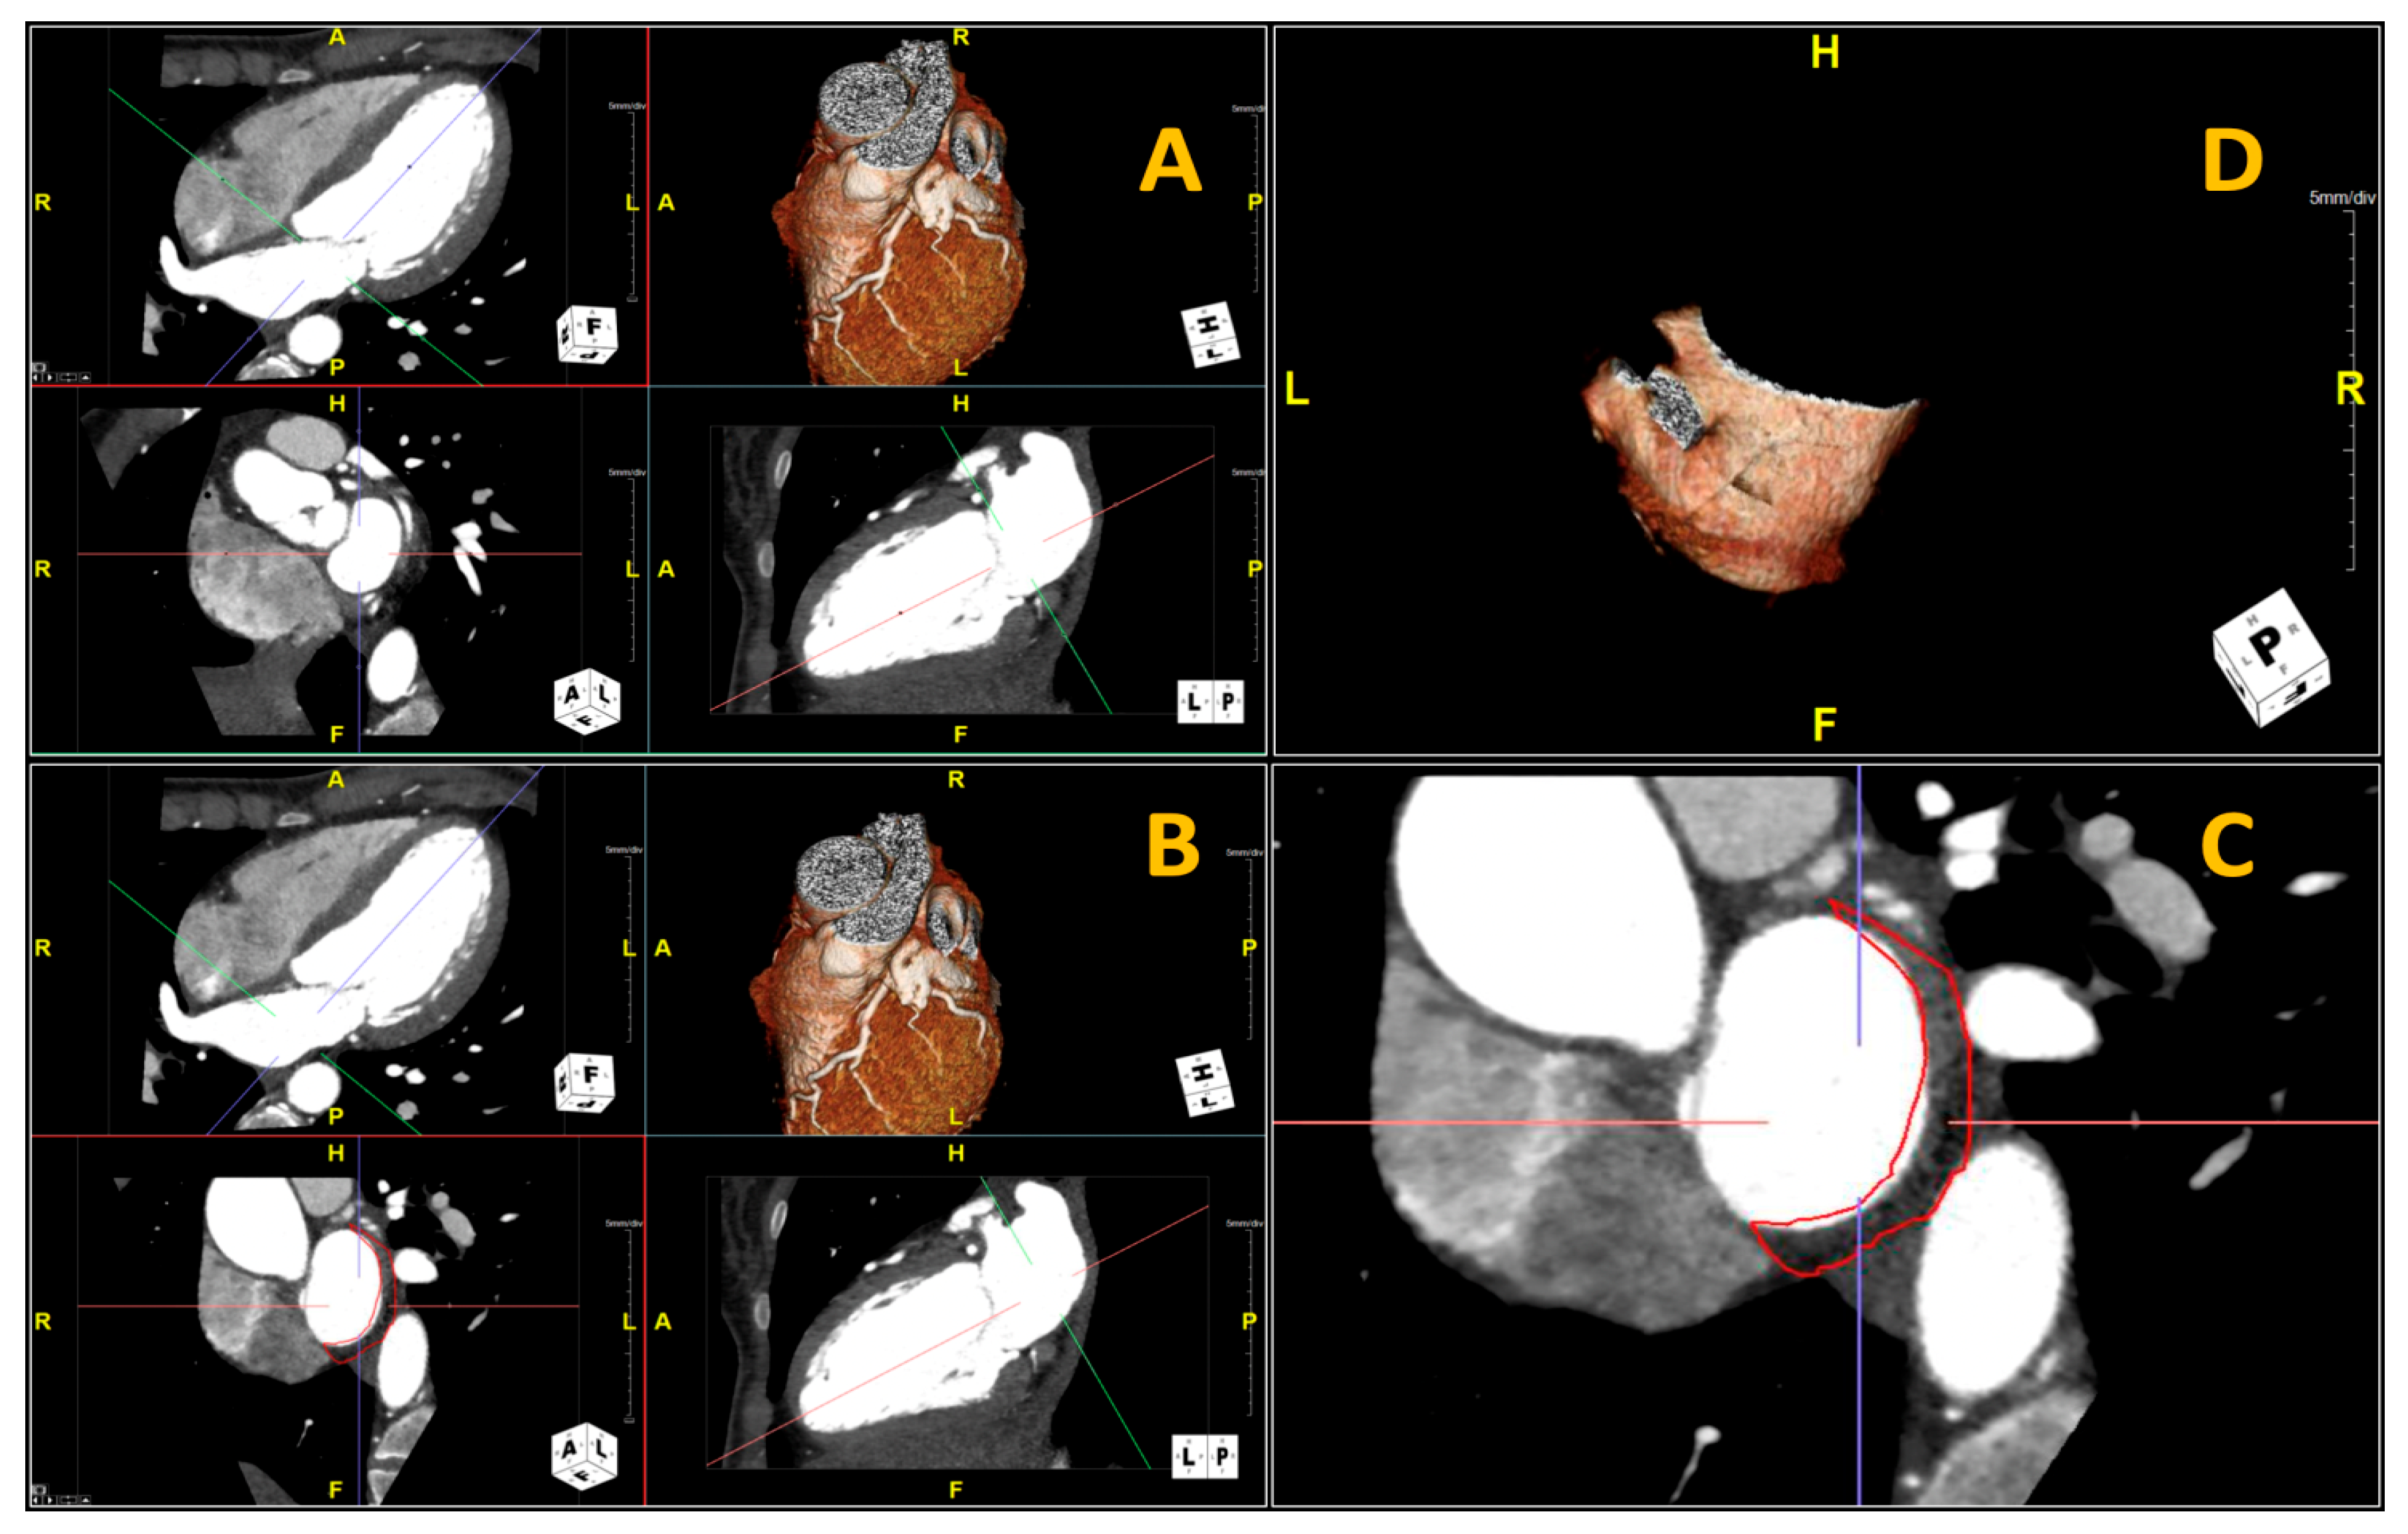

2.3. Fat-LA Volume and Attenuation

3.2. Posterior LA Adipose Tissue CTA Volume and Attenuation